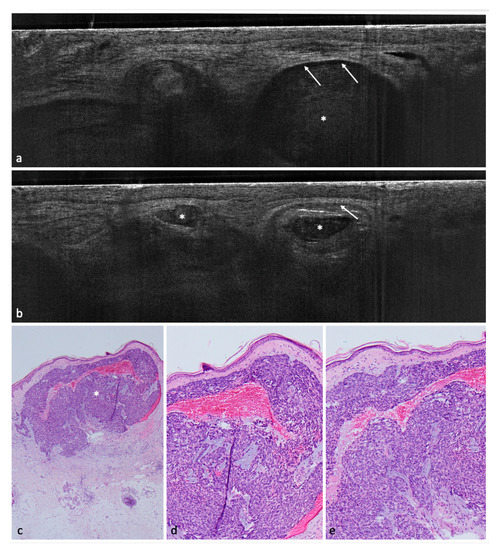

Figure 1. Nodular BCC on the lower leg of a 68-year-old female patient. (a,b) LC-OCT images. The nodular BCC presents itself with a fine granular texture corresponding to basaloid cells, peritumoral clefting (white arrows) and homogeneous areas with possibly liquefactive necrosis with remaining cell debris (white asterisks). (c) (40×), (d) (100×), and (e) (100×): corresponding histological HE-stained sections with peripheral palisading, clefting, and a central necrosis.

Concerning BCC subtypes, following parameters were inserted in the logistic regression: thinning of the epidermis, shoal of fish pattern of the lobules, and string of pearls pattern of the lobules. After logistic regression, thinning of the epidermis and string of pearls were the most impactful key criteria to influence the distinction between superficial BCC and other BCC subtypes (Figure 1, Figure 2 and Figure 3).

In a second step, we tried to identify with the help of logistic regressions a few key criteria able to distinguish between BCC and non-BCCs; these were: poorly defined DEJ, hyporeflective ovoid structures or nests/lobules (Figure 3), and dark rim/clefting (Figure 1). These criteria were consistent with previous findings [10,11].